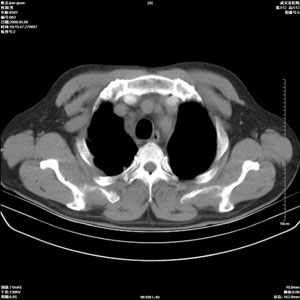

病人 男 60岁 主诉 胸闷 无明显发热 一般情况尚可。

1.右上肺陈旧性肺结核.

2.心脏增大(以左心室增大为著),请结合b超及听诊.

1.两上肺陈旧性结核;慢支肺气肿。

2.肺门血管扩张,心脏增大,为肺心病

1.陈旧肺结核;

2.慢支肺气肿;

3.肺心病.

陈旧性肺结核,左心房扩大,左心衰竭